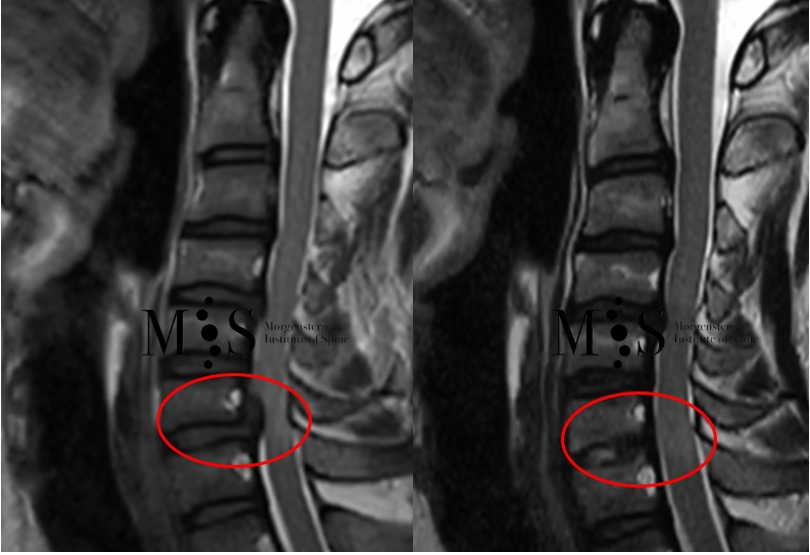

Imagen izquierda: Imagen de RMN de una compresión de la médula cervical en nivel C6/C7 (marcada con el círculo rojo) con signos de mielopatía. Imagen derecha: imagen de control de RMN del mismo paciente 2 meses después de la cirugía en la que se observa la completa descompresión y liberación de la médula espinal.